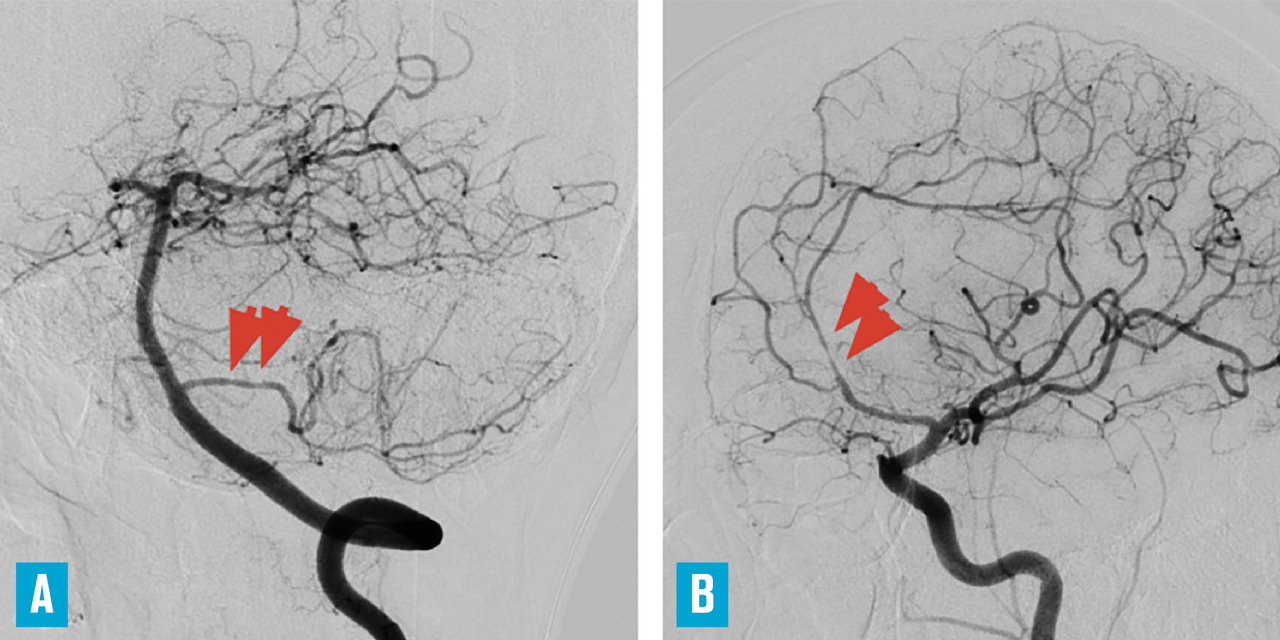

Cet examen reste néanmoins l’exploration artérielle de référence.2 Le risque du cathétérisme est extrêmement faible chez un patient jeune sans athérosclérose ni trouble de la coagulation. Pour que la sensibilité de l’examen soit optimale, l’examen doit être réalisé selon une technique parfaite, avec exploration des quatre axes. L’aspect caractéristique d’une vascularite primitive du système nerveux central associe des rétrécissements artériels segmentaires et étagés avec parfois des dilatations fusiformes interposées, des occlusions distales et des irrégularités pariétales (Explorations extraneurologiques

La présence de rétrécissements segmentaires étagés sur les artères intracrâniennes n’est pas spécifique des vascularites cérébrales : outre le syndrome de vasoconstriction cérébrale réversible déjà évoqué (v . tableau ), il peut s’agir d’emboles multiples en voie de recanalisation (origine cardiaque ou artérielle) ou de sténoses athéromateuses. L’atteinte prédominante sur les artères de gros et de moyen calibre, la présence de facteurs de risque vasculaire et des calcifications sur les parois artérielles à la tomodensitométrie cérébrale sont autant d’arguments en faveur d’une athérosclérose intracrânienne, que l’on rencontre en particulier chez les sujets non caucasiens (africains et asiatiques) et chez les diabétiques.2 En cas de difficulté diagnostique, la répétition des explorations artérielles aide à rattacher des anomalies artérielles à une vascularite, en montrant leurs modifications (amélioration ou aggravation) en quelques semaines.

La présence de rétrécissements segmentaires étagés sur les artères intracrâniennes n’est pas spécifique des vascularites cérébrales : outre le syndrome de vasoconstriction cérébrale réversible déjà évoqué (